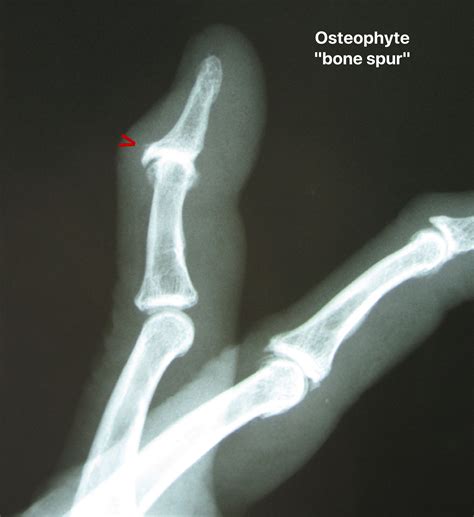

If you have ever experienced unexplained joint pain, stiffness, or a nagging sensation that something is "catching" in your movement, you may have encountered a condition involving bone spurs. Many people wonder, what is an osteophyte, and how does it affect their daily mobility? Simply put, an osteophyte is a bony projection that develops along the edges of joints. While they are often associated with the natural aging process and wear-and-tear conditions like osteoarthritis, understanding their formation, symptoms, and management is crucial for maintaining joint health as you age.

To fully grasp what is an osteophyte, it is helpful to visualize how your joints function. Joints rely on smooth cartilage to cushion the bones and allow for seamless motion. Over time, or due to injury, this cartilage can begin to break down. When the body senses this degradation, it attempts to "repair" the area by producing extra bone material. These smooth, hard bumps—the osteophytes—are the result of the body’s attempt to increase the surface area of the joint to distribute pressure more evenly.

• The Fingers: Commonly appearing as small, hard knobs at the joints near the fingertips (Heberden’s nodes).

Doctors typically diagnose these bone spurs through a physical examination and imaging techniques such as X-rays, MRIs, or CT scans. These images allow medical professionals to visualize the size and exact location of the growth, which helps in formulating an effective treatment plan.

💡 Note: While they are often referred to as "bone spurs," osteophytes are not sharp or jagged in most cases; they are usually smooth, calcified growths that form slowly over months or years.